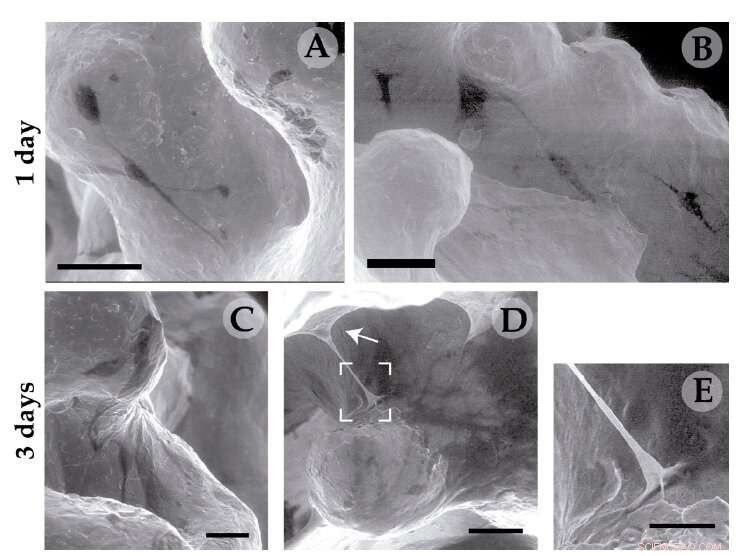

Electron microscopy of human osteoblastic cells with titanium disks and coated by the structure 1 and 3 days after the implant. Credit: Fundación Descubre

In this way, each branch of the scaffold becomes attached to the bone with these hooks, thereby anchoring the implant and assisting the connections to occur naturally thanks to the integration of the metal with the living tissue. "These unique properties make dendrimeric systems suitable for a wide variety of applications in regenerative medicine," added the researcher.